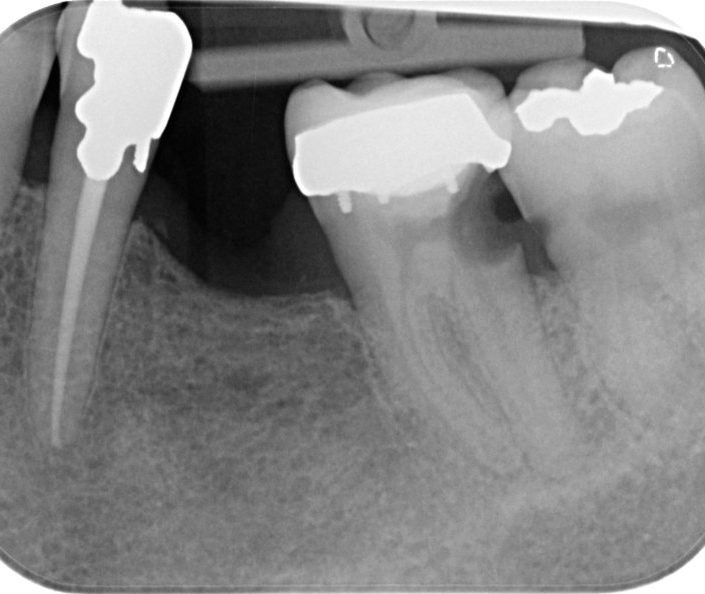

The X-rays showed a cavity where he shoved his probe. David then said that he felt responsible and decided to extract the tooth or offered the alternative of “£1000 dental heroics” that ‘may not work and I may end up losing the tooth anyway. ‘